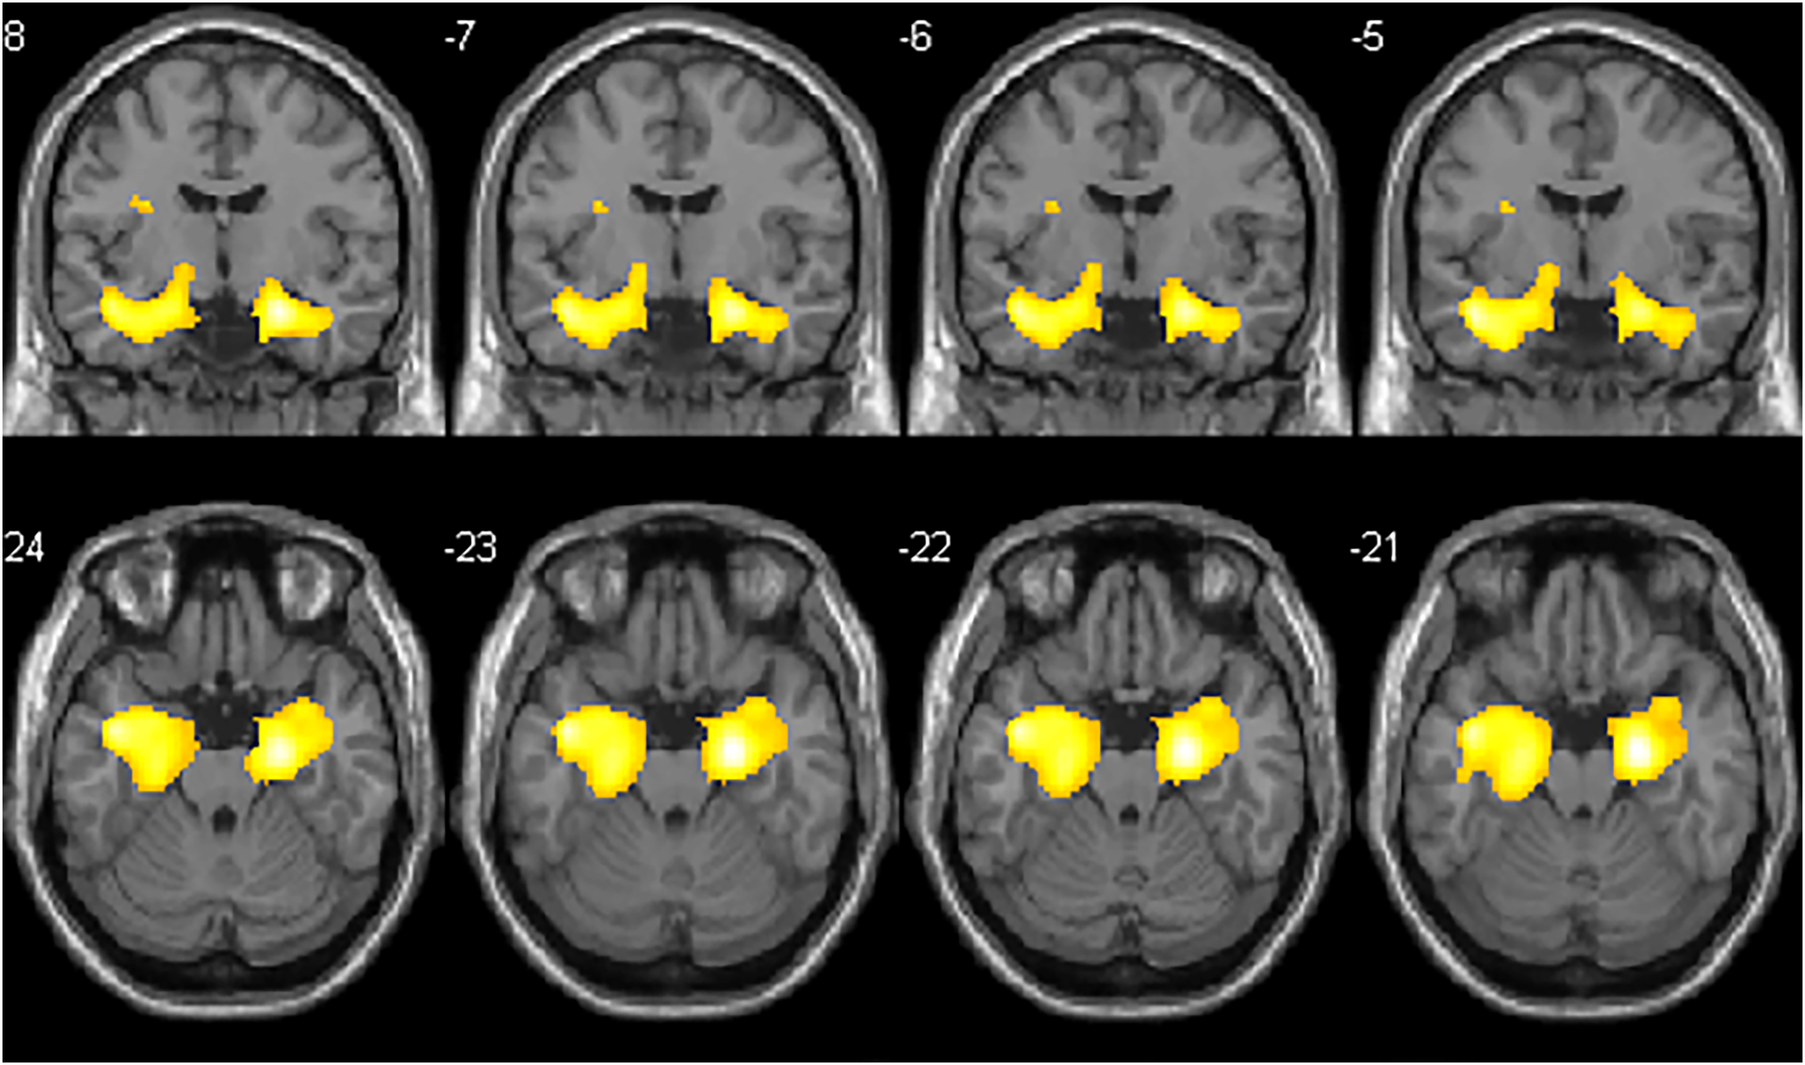

Visual analysis of PET images showed a moderate reduction in 18F-FDG uptake in the bilateral mesial-temporal region (Figure 1); these findings were confirmed by the voxel-wise analysis. The SPM8 analysis showed, at a height threshold of p < 0.001 (uncorrected), a significant hypometabolism (p < 0.001) in both patients (n = 2), as compared to healthy subjects (n = 19), in the left and right mesial-temporal regions with a peak in the bilateral hippocampus (right: MNI coordinates 22/-12/-20 mm with a T-score of 6.7; left: MNI coordinates −20/−16/−19 mm with a T-score of 6.1; Figure 2).

Figure 1. Axial PET slices showing areas of moderate glucose hypometabolism in bilateral mesial brain regions in case 1 (A) and case 2 (B).

Figure 2. Coronal and axial slices showing SPM areas of reduced brain metabolism superimposed on a T1 axial magnetic resonance reference atlas. The colored areas indicate the locations where the voxel values of both patients are significantly hypometabolic compared to healthy subjects (P < 0.001). The t-values are represented by the brightness of the color.